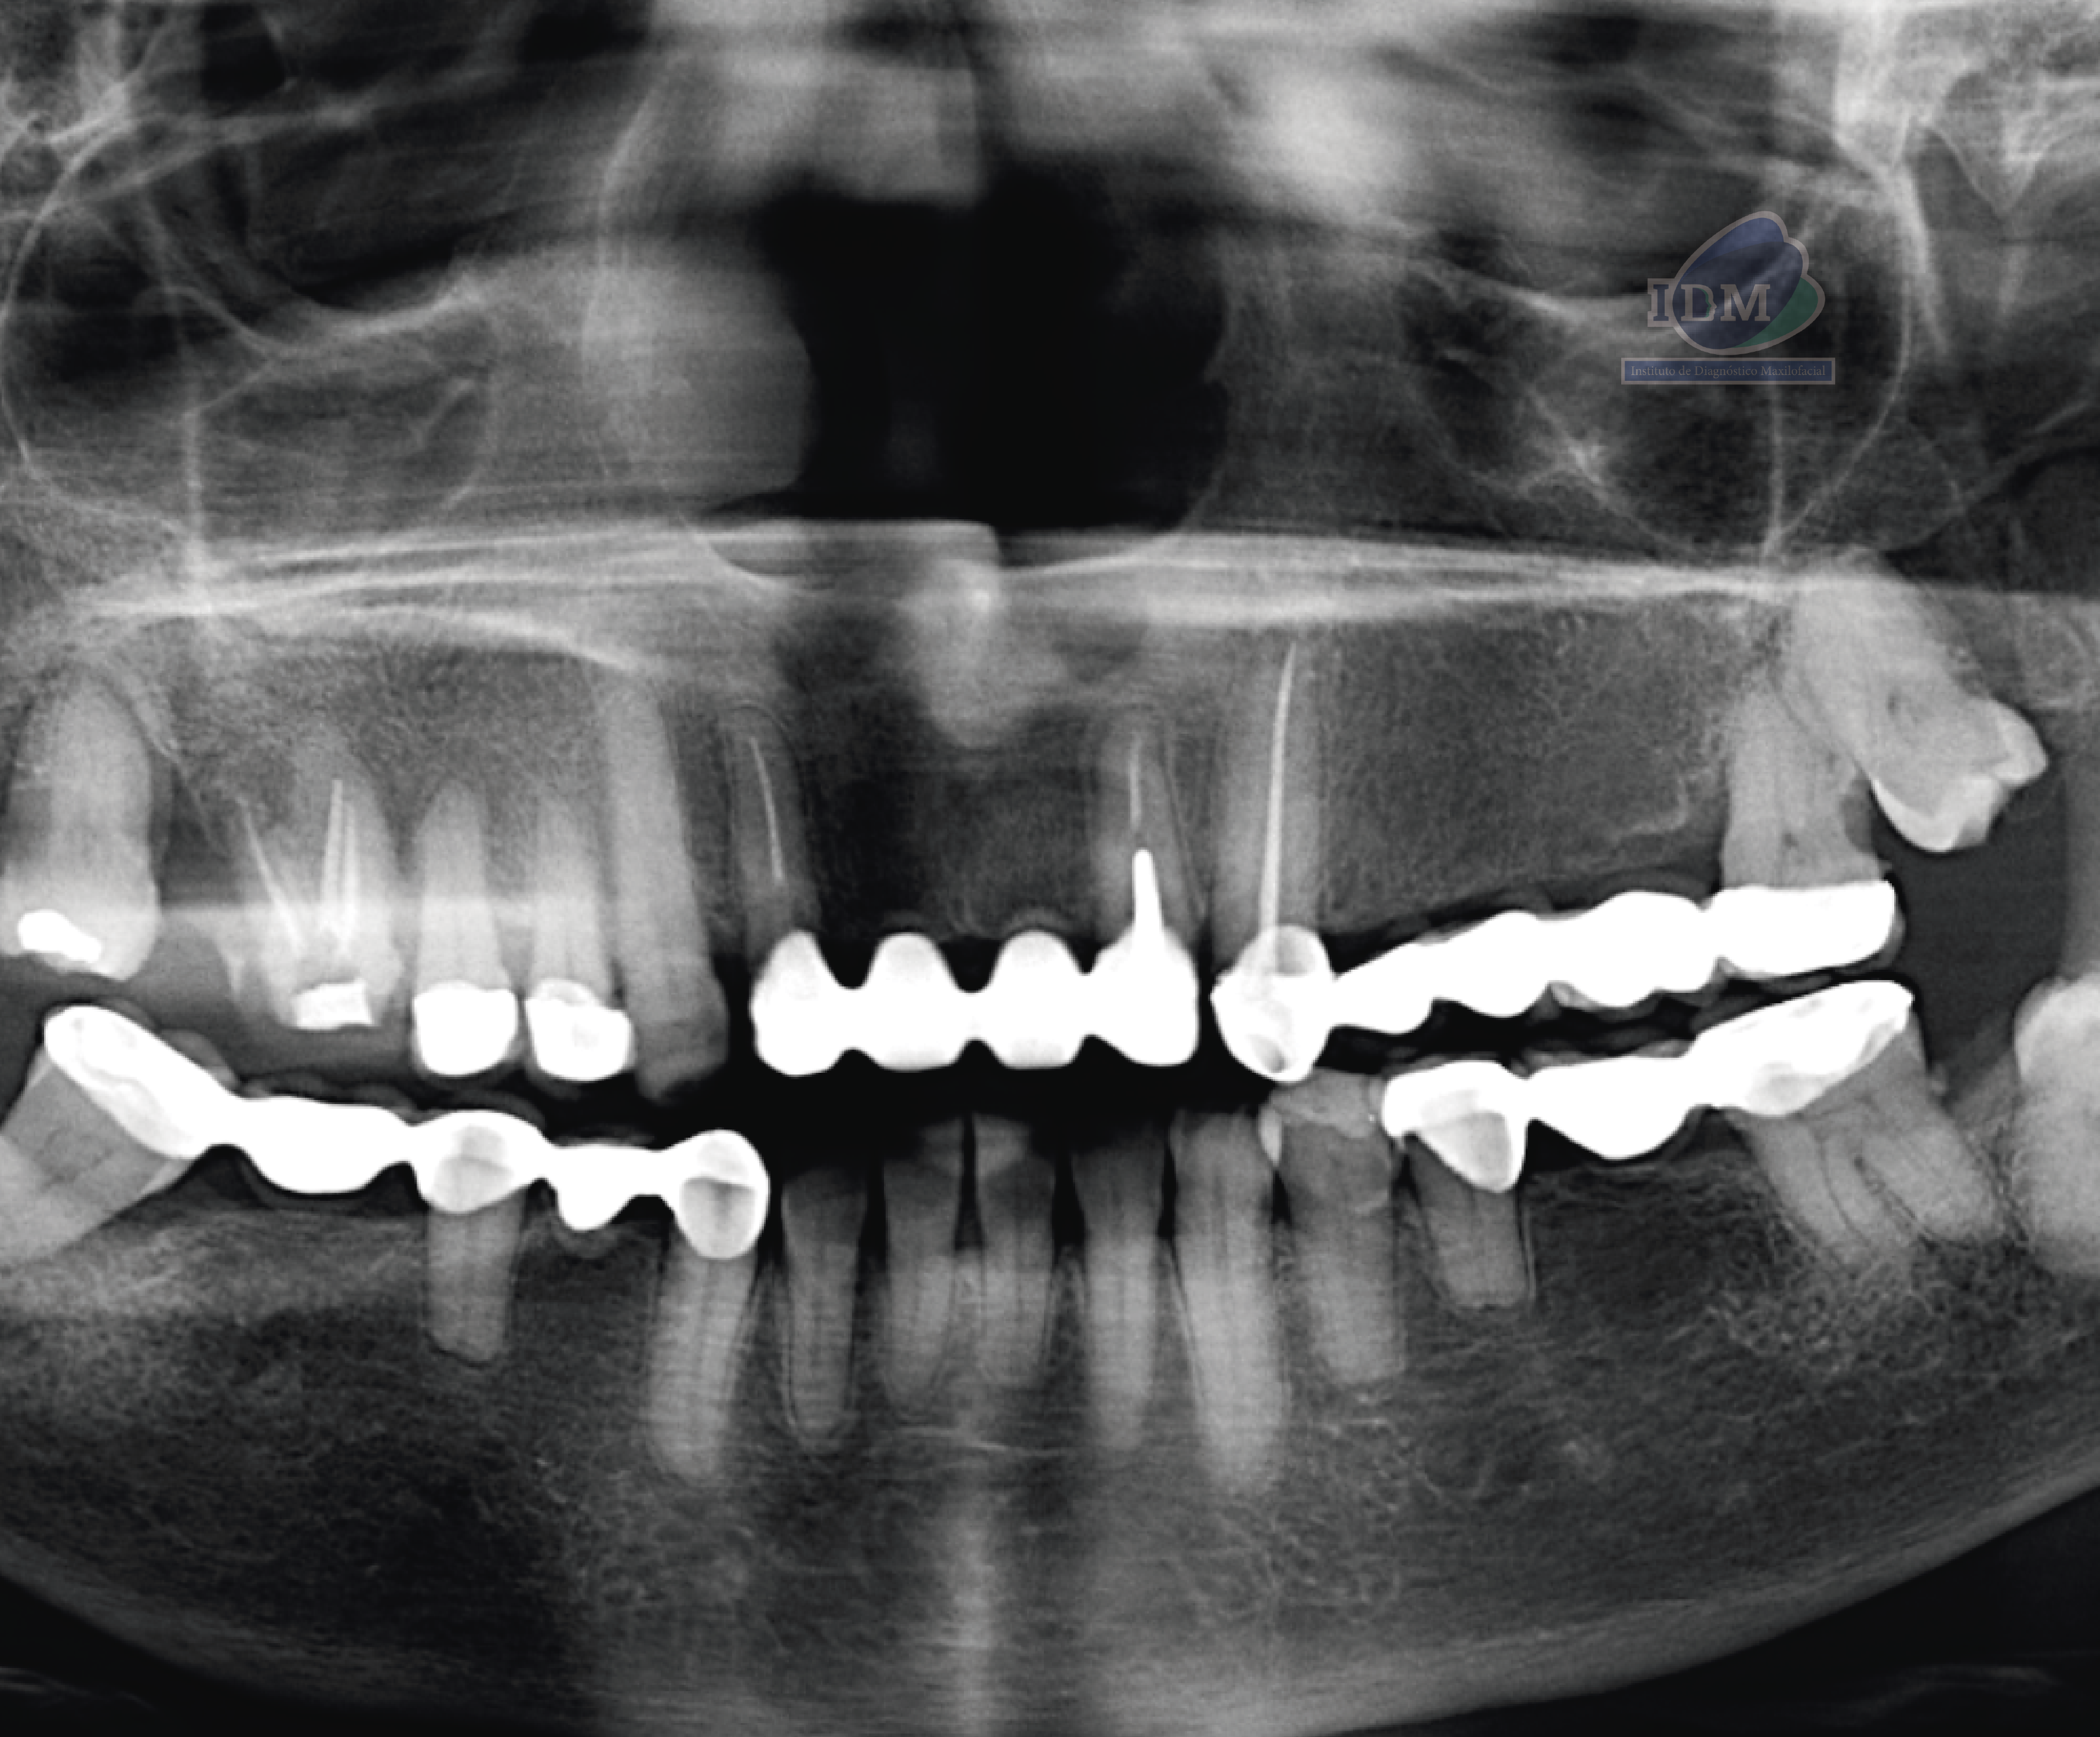

Paciente femenina de 72 años acude a IDM para realizarse una tomografía para evaluación general, al observar la radiografía panorámica se puede observar una mineralización del proceso estilohioideo del lado derecho, aplanamiento del contorno condilar del lado derecho, presencia de placa mineralizada y rebasorción alveolar con presencia de contornos irregulares, múltiples coronas protésicas y piezas dentarias 16, 12, 21, 23 con obturación de conductos, asi como la retención de la pieza 38 y su Hipercementosis, etc.

Sin embargo a nivel de la rama mandibular del lado derecho se observan múltiples imágenes radiopacas de forma irregular que a su vez ocasionan imágenes fantasmas en el lado contra lateral.

Radiografia Panorámica